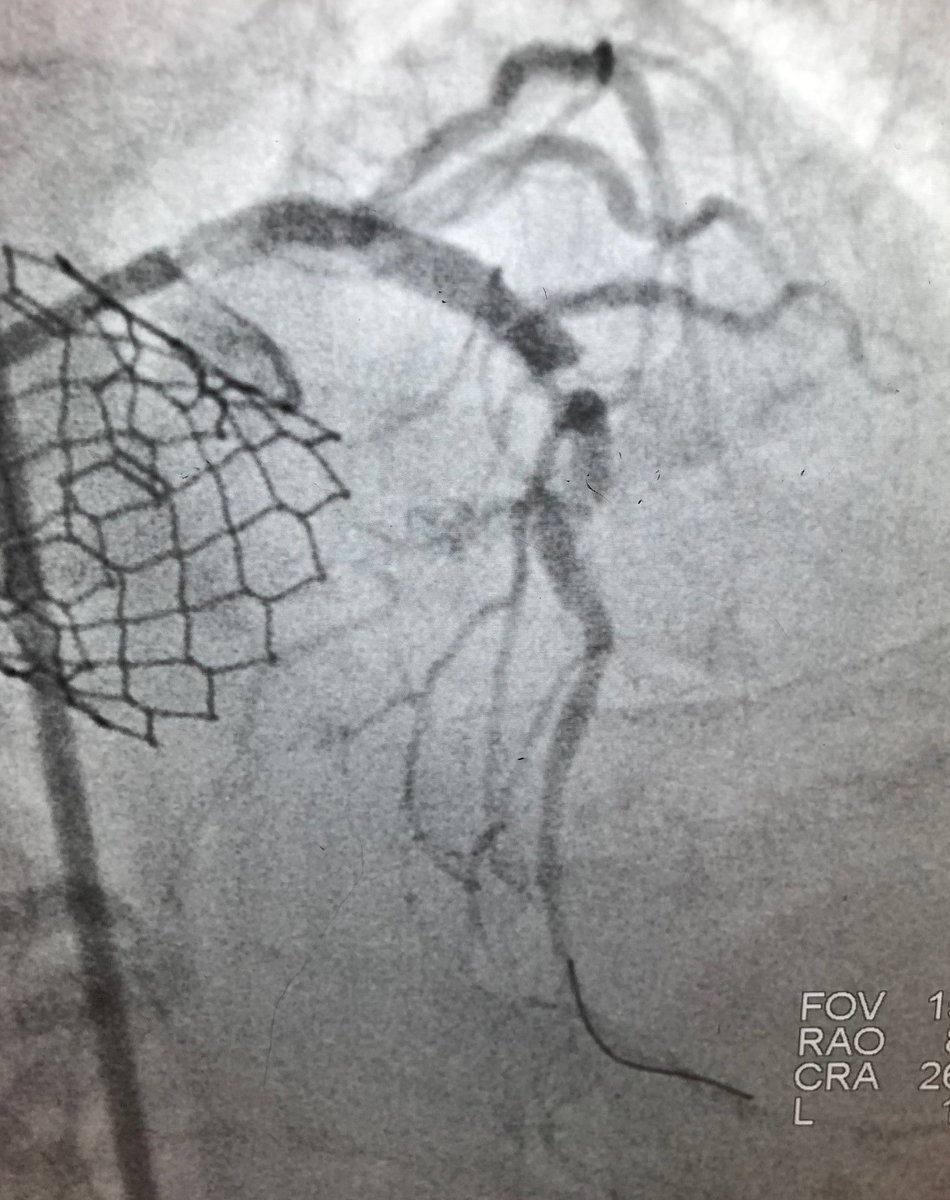

Great #RotaShock live case at #SIF2023 by Drs @AlokSharma081 @Herms2James @RizikMd & Richard Shlofmitz. Imaging with #OCT & #IVUS, @HonorHealth team used a 3.0 & 4.0 #ShockwaveC2 to treat concentric LAD Ca2+ & LM nodular Ca2+ for an excellent result! ISI bit.ly/3iEq7fc

ShockwaveIVL's tweet image. Great #RotaShock live case at #SIF2023 by Drs @AlokSharma081 @Herms2James @RizikMd & Richard Shlofmitz. Imaging with #OCT & #IVUS, @HonorHealth team used a 3.0 & 4.0 #ShockwaveC2 to treat concentric LAD Ca2+ & LM nodular Ca2+ for an excellent result!